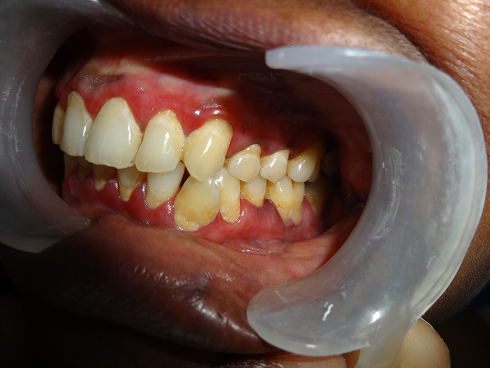

aphthous ulcers

desquamative gingivitid